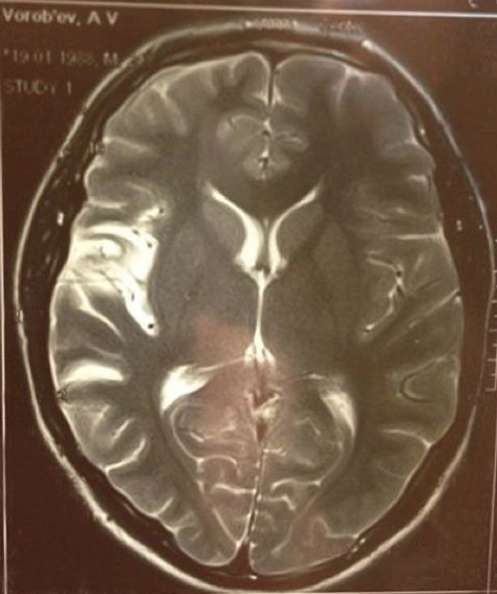

«От „точки невозврата“ прошло 3 года и несколько дней. Жизнь удивительная штука, я вам скажу. Мой поражённый на 25% мозг работает ещё быстрее, чем когда-либо. Я бегаю, прыгаю, пою и танцую, пишу музыку, снимаюсь в кино и снимаю его сам. И иногда на концертах пою мимо нот, так как больше не слышу этого, потому что восстановиться на 100% уже невозможно. Иногда не могу подняться по лестнице, потому что сердце так колотится, что чуть не разбивает грудную клетку изнутри, приходится сидеть на ступеньках, смотреть на подрагивающие руки и, смеясь над собой, мечтать о законопроекте, который вообще отменит лестницы:) Пью таблетки для разжижения крови, и живу полной жизнью, — каждый день, не ограничивая себя ни в чем. Организм перестал нуждаться в отдыхе, и вообще перестал требовать время на сон без снотворного, и это дарит много времени, которое не хочется терять. Мне повезло быть молодым, когда случился инсульт, и ещё больше повезло остаться жить. Я научился ценить жизнь и время, которое нам всем отведено на земле. Жизнь действительно удивительная штука, и она, действительно, похожа на коробку конфет, — иногда эти конфеты горькие, и дарят только боль, иногда — сладкие, как поцелуй любимой женщины… Но эта коробка никогда не пуста. Я совершенно точно понял одно- если и есть Бог, то он очень любит меня:)» — откровенно написал артист.